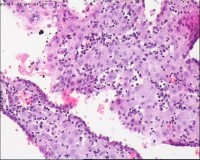

性别

女

年龄

20岁

临床诊断

一般病史

停经3月,阴道不规则流血7天。

标本名称

宫刮物

大体所见

灰白灰红碎组织一堆,大小为7*6*1cm,部分组织呈水泡状

流产残余物。

水肿的绒毛和蜕膜,没看到增生的滋养细胞。必要时可做IHC除外部分葡萄胎,并结合临床HCG。

考虑葡萄胎